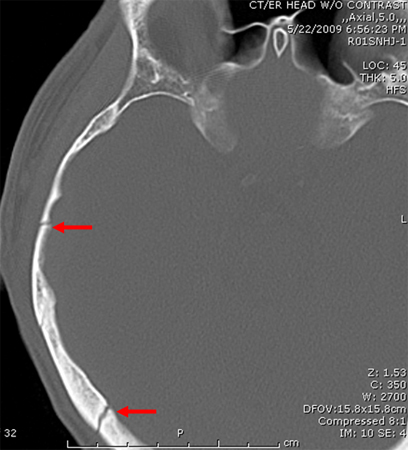

Sagittal CT images of an open, comminuted, depressed skull fracture. Note the associated pneumocephalus (small arrows). The level of depression is greater than the bony table and there are several bone fragments impacted below the inner cortex of the opposing bone (large arrow). Despite lack of underlying associated brain injury this fracture required operative debridement and elevation of the bone fragments. See also the corresponding coronal CT image

From the teaching collection of Demetrios Demetriades; used with permission